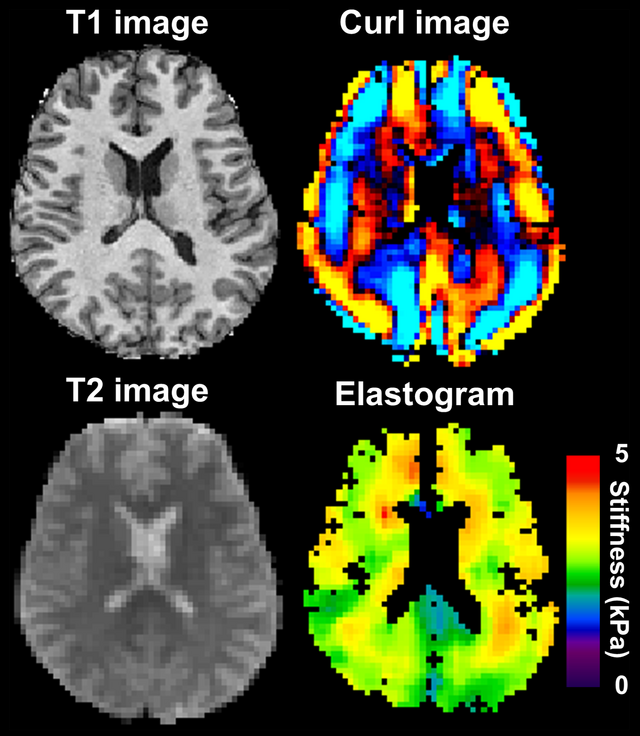

Beyond individual spikes of dopamine, music can pull entire networks of brain cells into synchronized rhythms, a kind of internal echo of the external beat. Using techniques like electroencephalography and magnetoencephalography, researchers have shown that brain waves in certain frequency bands lock onto musical timing and structure. When people listen to complex or emotionally charged passages, these neural oscillations can become more coordinated, especially across areas involved in hearing, movement, and emotion.

Some studies have found that low-frequency brain waves align with the beat and phrasing of the music, while faster rhythms reflect finer details like melody and timbre. In moments that listeners later describe as intensely moving, patterns of activity can shift rapidly, as if the brain is reconfiguring to process something especially salient. While scientists are still mapping the exact signatures of goosebump moments, the emerging picture is that our brains do not just hear music; they actively ride it, surfing incoming waves of sound with their own waves of electrical activity.